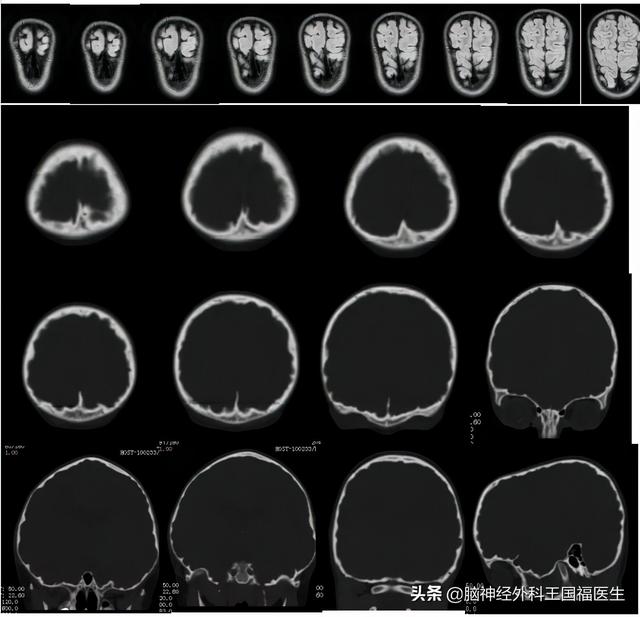

于是给小刚进行了外显子基因的筛查,结果显示的确存在导致颅缝早闭的致病基因,同时并未发现有导致癫痫的基因存在,提示患儿的癫痫是后天继发的可能性极大,儿童神经内科和儿童神经外科的大夫继续调查患儿的发病历史,抽丝剥茧从海量记录中找到了患儿在1岁和4岁时留下的影像资料,回顾这些资料,颅缝早闭开始漏出了它的马脚……

在患儿一岁时曾经因为“中耳炎”做过一次头颅CT检查,从这张片子分析,出现冠状缝和矢状缝,至少在能看到的部分层面上,是没有闭合的。

而在患儿4岁时,复查耳部CT,则可以看出头颅的外形已经开始改变,在颅骨内板上已经出现了对脑组织的压迫征象,这些像连续小锯齿一样的边缘,就是脑组织在坚硬的颅骨内板上压出来的痕迹。

而现在呢,明显的头颅已经呈前后径明显拉长的舟状颅,颅骨内板上已经布满了脑组织压迫所出现的压痕。